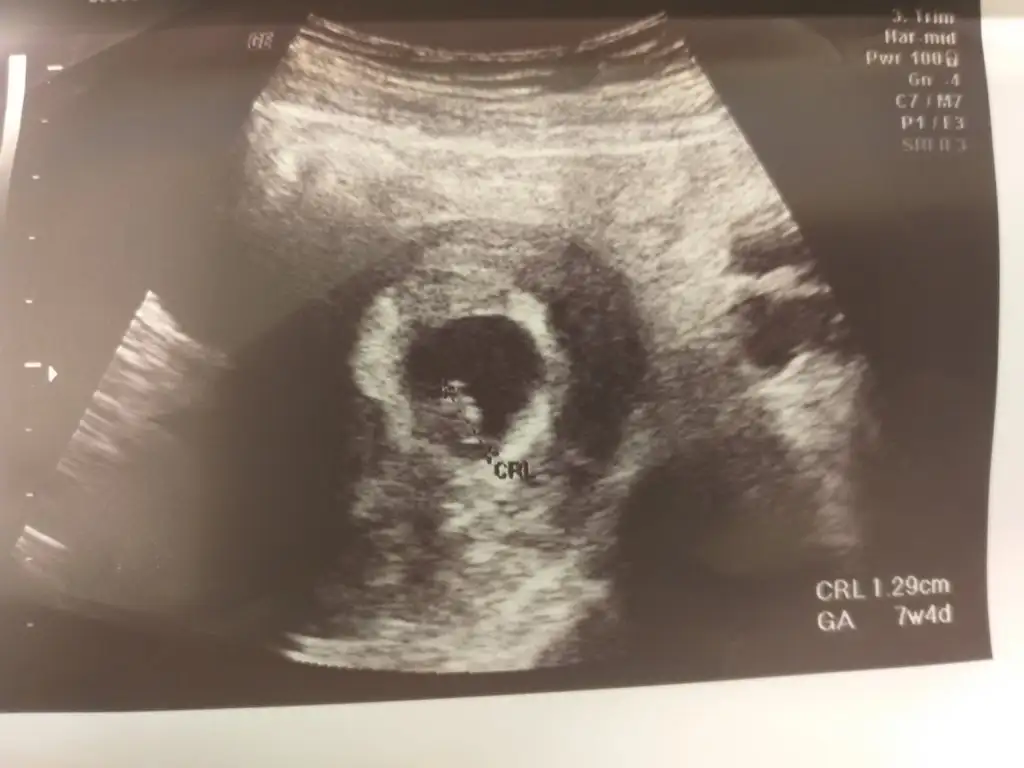

Kizlar banada yorum lutfen 1.resim 6 haftalik vajinal

2.resim 7 haftalik karindan usg

3 resimde 9 haftalik karindan yorumlarsaniz cok sevinirimmm